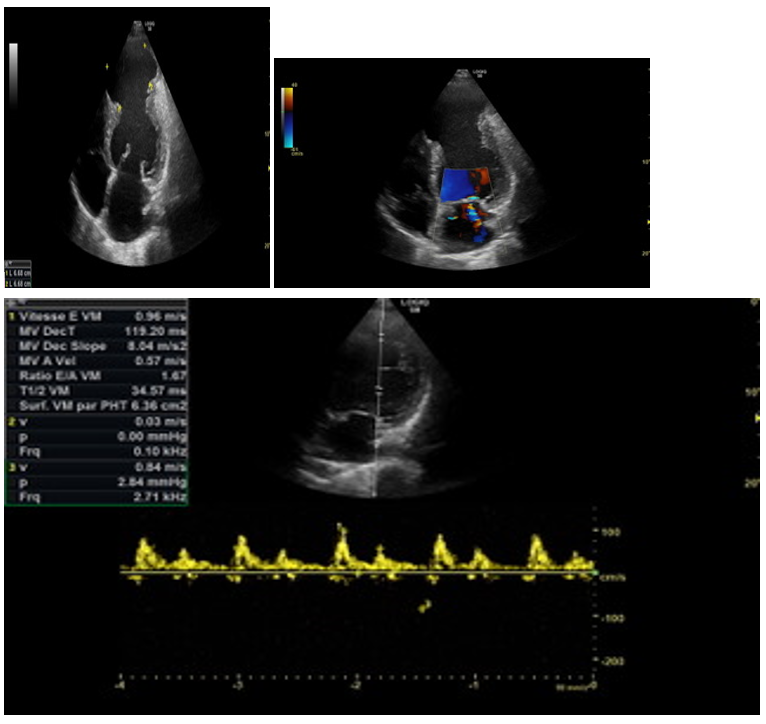

Aneurysm of the Left Ventricle Revealed by a Coronary Syndrome Complicated by Cardiogenic Shock

Ziani Hicham, Aberouch Larbi, Nabil Lacchab, Jaouad Ngadi, Aziza Bentalha, Taddili Jawad and Mamoun Faroudy